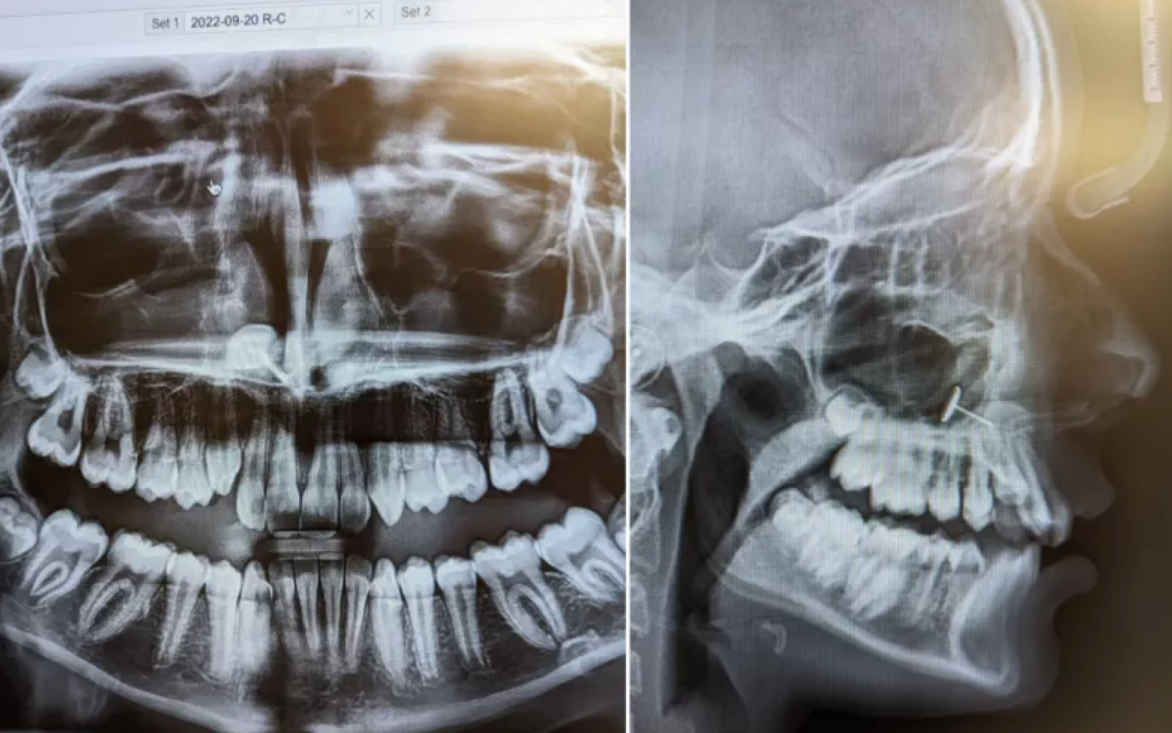

«Ο ορθοδοντικός επέστρεψε στο δωμάτιο και έβαλε τις ακτινογραφίες στην οθόνη», είπε η Οφέλια στο Newsweek. «Τις είδαμε όλοι ταυτόχρονα και πέρασαν αρκετά λεπτά προσπαθώντας να καταλάβουμε τι βλέπαμε».

Αυτό που έβλεπαν φαινόταν να είναι ένα μικρό κομμάτι μετάλλου που είχε σφηνωθεί στα ιγμόρεια της μύτης της κόρης της. Η Οφέλια δεν είχε ιδέα πώς βρέθηκε εκεί, αλλά η κόρη της ήξερε ακριβώς τι είχε συμβεί.

Όλα αυτά μέχρι την επίμαχη επίσκεψη στον ορθοδοντικό και την ακτινογραφία που αποκάλυψε τα πάντα. Η Οφέλια δημοσίευσε τις εικόνες των ακτινογραφιών στον λογαριασμό της στο Reddit, που έγιναν αμέσως viral.